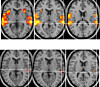

This article was produced and financed by The Research Council of Norway When hallucinatory voices suppress real ones